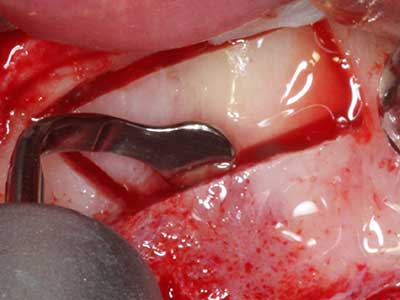

La preparación de la ventana lateral en la elevación del suelo del seno maxilar representa un enorme reto, sobre todo para profesionales de la implantalogía que tienen poca experiencia en técnicas quirúrgicas. Retirar la cobertura ósea del seno maxilar sin provocar daños en la membrana de Schneider es tan solo una parte de la operación; tras crear un acceso suficiente, es preciso movilizar con cuidado la mucosa del seno maxilar a fin de dejar espacio para el material o los implantes que vayan a incorporarse. En esta aplicación la cirugía piezoeléctrica resulta útil en dos sentidos: por un lado, el uso de insertos diamantados permite realizar una retirada selectiva del hueso y, si se actúa con cuidado, la membrana permanece intacta, y por otro lado, las frecuencias de ultrasonidos favorecen también un desprendimiento sin problemas de la membrana, pues se transfieren al espacio comprendido entre la mucosa y el suelo del seno maxilar gracias al uso de piezas romas especiales (Cassetta, Ricci et al. 2012, Pereira, Gealh et al. 2014) (Rickert, Vissink et al. 2013). De este modo, no es de extrañar los trabajos publicados en la actualidad sobre la técnica de elevación del suelo del seno maxilar mediante la técnica de Caldwell-Luc con instrumentos piezoeléctricos (Wallace, Tarnow et al. 2012).

En la extracción de bloques óseos la piezocirugía también presenta ventajas adicionales: Además de la alta precisión en la osteotomía que ya se ha descrito antes, se ha comprobado que el uso de los delgados insertos de sierra resulta especialmente cuidadosas con el hueso. Frente a esto, sobre todo cuando se usan las fresas de Lindemann, cabe esperar pérdidas en la extracción significativamente más altas debido al mayor grosor de la parte frontal del cabezal (Lakshmiganthan, Gokulanathan et al. 2012). La separación basal que se necesita en particular en los injertos de bloque extraídos de forma retromolar se ve facilitada mediante sierras perpendiculares especialmente previstas a tal fin, lo que permite considerar que la cirugía piezoeléctrica es un procedimiento preciso y seguro para la obtención de bloques de hueso en el área retromolar (Happe 2007) (fig. 1-12).